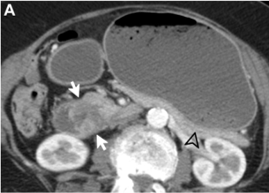

In the pure form, the appearance can range from ill-defined fat stranding and inflammatory change in the groove between the pancreatic head and duodenum, to frank soft tissue in the groove.

This soft tissue often has a “sheetlike” curvilinear crescentic shape that is best appreciated on coronal images.

If multiphase imaging is performed, this soft tissue tends to show increasing delayed enhancement as a result of a significant fibrotic component.

There can be of the medial duodenal wall (particularly on the coronal images), and small cysts are a common feature either within the thickened duodenal wall or the pancreaticoduodenal groove itself.